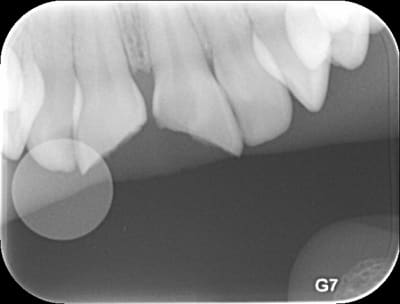

Jeune patiente de 11 ans, chute il y a 72h. Fractures coronaires de 11 et 21.

Pas de vraie exposition mais le tissu pulpaire est visible par transparence au niveau des traits de fracture.

(La radio est horrible, je sais...)